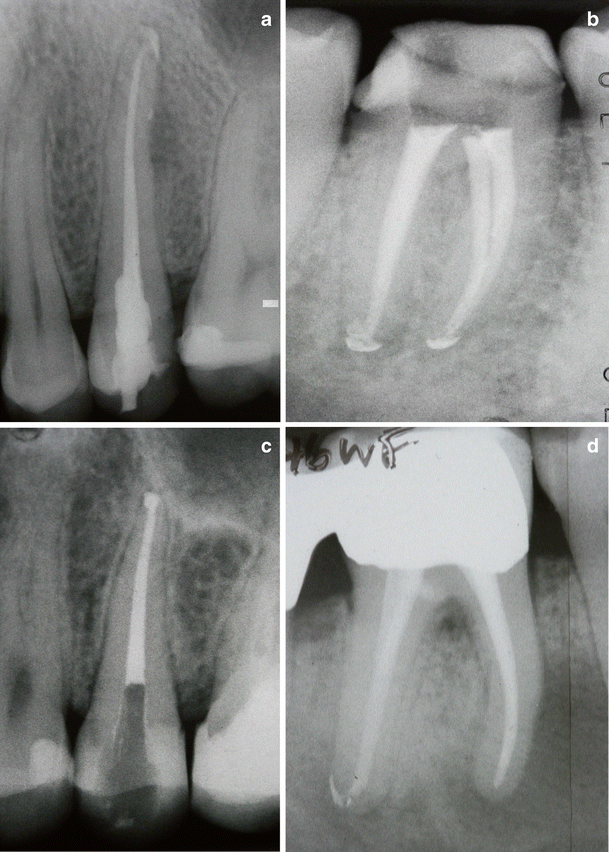

Filling root canals in 3 dimensions Endodontic techniques Root Canal Technique A root canal is performed when the endodontist removes the infected pulp and nerve in the root of the tooth, cleans and shapes the inside of the root canal, then fills and seals the space. Endodontists and dentists do about 15 million root canals. A root canal treatment is a dental procedure to remove inflamed or infected pulp on the. Root Canal Technique.

Figure 1 from Reciprocating root canal technique induces greater debris Root Canal Technique A root canal is a dental procedure involving the removal of the soft center of the tooth, the pulp. A root canal is performed when the endodontist removes the infected pulp and nerve in the root of the tooth, cleans and shapes the inside of the root canal, then fills and seals the space. Endodontists and dentists do about 15. Root Canal Technique.